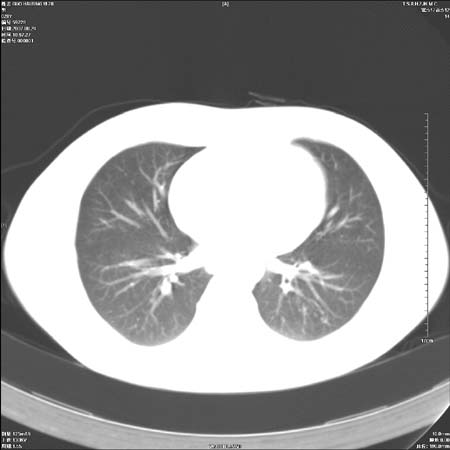

本例倾向周围型肺癌

鉴别:中央型肺癌-肿块那么明显一般合并节段肺不张或阻塞性炎症。

本例肿块边缘外侧可见左上叶各段支气管。

肺癌可能性大。(有分叶,毛刺)

左侧肺门区见一块状病灶可见分叶,纵隔内及左肺门见肿大淋巴结,应该是周围型肺癌而不是中心型肺癌,原因有以下2点,1未见阻塞肺气肿和阻塞性炎症,这么大肿块如果是中心型肺癌就是未分化型或小细胞型肺癌不出现阻塞性肺不张也应该有阻塞炎症或阻塞性肺气肿,2如果是中心型肺癌临床出现最早的症状是咳嗽(此时可无任何异常影象),而此人这么大肿块只有背部隐痛是体检才发现无法解释.